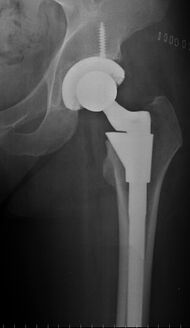

Post-operative projectional radiography is routinely performed to ensure proper configuration of hip prostheses.

The direction of the acetabular cup influences the range of motion of the leg, and also affects the risk of dislocation.[7] For this purpose, the acetabular inclination and the acetabular anteversion are measurements of cup angulation in the coronal plane and the sagittal plane, respectively.

Acetabular inclination.[78] This parameter is calculated on an anteroposterior radiograph as the angle between a line through the lateral and medial margins of the acetabular cup and the transischial line which is tangential to the inferior margins of the ischium bones.[78]

Acetabular inclination is normally between 30 and 50°.[78] A larger angle increases the risk of dislocation.[7]

Acetabular anteversion.[79] This parameter is calculated on a lateral radiograph as the angle between the transverse plane and a line going through the (anterior and posterior) margins of the acetabular cup.[79]

Acetabular anteversion is normally between 5 and 25°.[7] An anteversion below or above this range increases the risk of dislocation.[7] There is an intra-individual variability in this method because the pelvis may be tilted in various degrees in relation to the transverse plane.[7]

Leg length discrepancy after hip replacement is calculated as the vertical distance between the middle of the minor trochanters, using the acetabular tear drops[78] or the transischial line[7] as references for the horizontal plane. A discrepancy of up to 1 cm is generally tolerated.[78][7]

Center of rotation: The horizontal center of rotation is calculated as the distance between the acetabular teardrop and the center of the head (or caput) of the prosthesis and/or the native femoral head on the contralateral side.[78] The vertical center of rotation instead uses the transischial line for reference.[78] The parameter should be equal on both sides.[78]